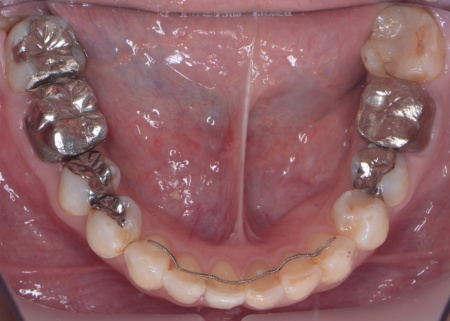

| カウンセリング | 拝見したところ、上前歯が大きく前に出ている上顎前突であり、上下の前歯が噛み合わずに口を閉じても前歯同士が接触しない「開咬(かいこう)」の状態でした。 レントゲン撮影をして詳しく調べた結果、歯の位置だけでなく、骨格的な問題があることが分かりました。 また、前歯で食べ物をうまく噛み切ることができないため、奥歯にも強い負担がかかっているだけでなく、このまま放置すると、奥歯がすり減ったり痛みが生じたりするリスクもあります。 以上のことから、噛み合わせを改善する治療が必要だと診断しました。 |

患者様の場合、骨格的な上顎前突が噛み合わせを乱している主な原因であることから、矯正治療では前歯を後方へ大きく動かすためのスペースを確保する必要があります。 そのため、今回は以下2つの方法を提案しました。 ①抜歯後、アンカースクリューを用いたワイヤー矯正 メリット:骨格的な上顎前突に対応しやすく、前歯を大きく後方へ動かすことができる ②取り外し可能な装置を使用するマウスピース矯正 メリット:装置が透明で目立ちにくく、取り外しができる 以上のメリットとデメリットを丁寧にお伝えしたところ、患者様は①のアンカースクリューを用いたワイヤー矯正を選択されました。 まず、上顎の左右奥歯を抜き、前歯を後方に動かすためのスペースを確保します。 治療の結果、前歯が正しく噛み合うようになり、横顔のバランスも整いました。 矯正治療終了後は、歯が元の場所に戻らないよう上下前歯に保定装置(リテーナー)を装着し、治療を終了しています。 |